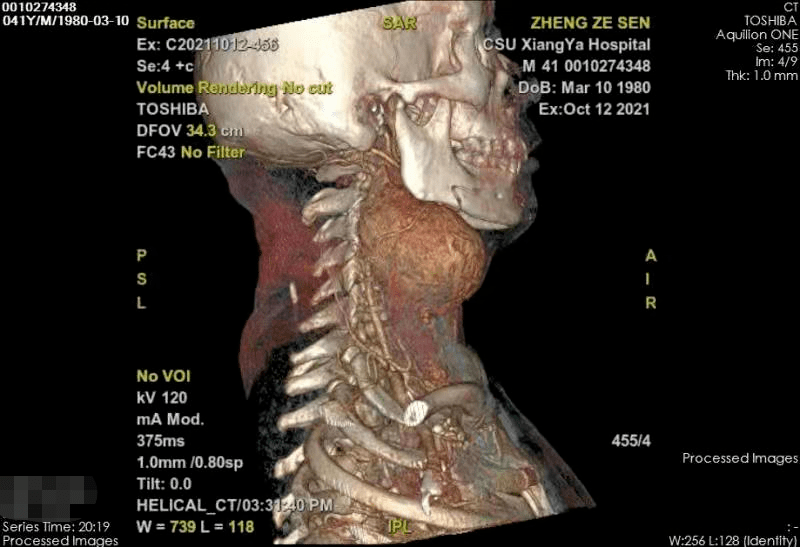

方先生入院后CTA及MRI的检查提示:颈动脉体瘤肿块大小为7.3X7.5X8.0CM , 为近颅底高位巨大颈动脉体瘤 , 肿瘤距离颅底仅1.5cm的空间 , 且瘤体供血异常丰富 , 瘤内多根血管充盈 。